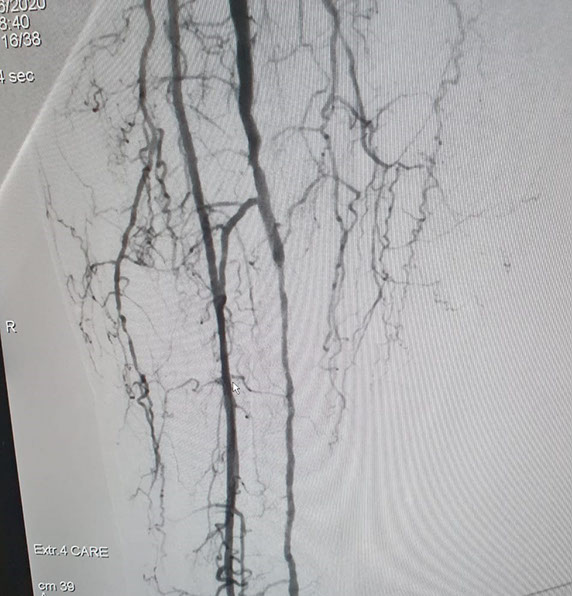

Las imágenes siguientes son previas al procedimiento y posterior se ve ambas arterias tíbiales permeables, y circulación en el pie